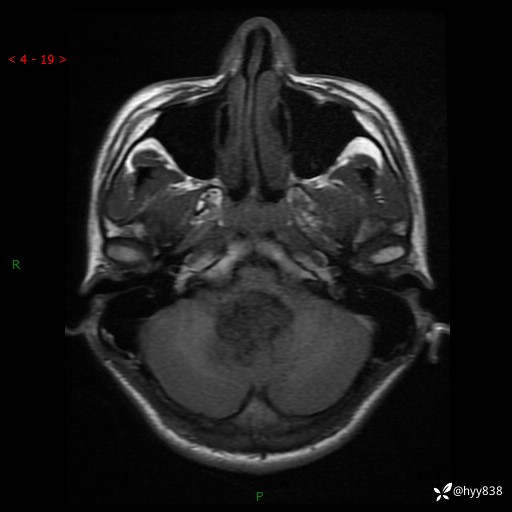

性别:男

年龄:17岁

简要病史:头痛伴间断性呕吐1月余,外院CT提示颅脑占位

颅脑MRI平扫+增强